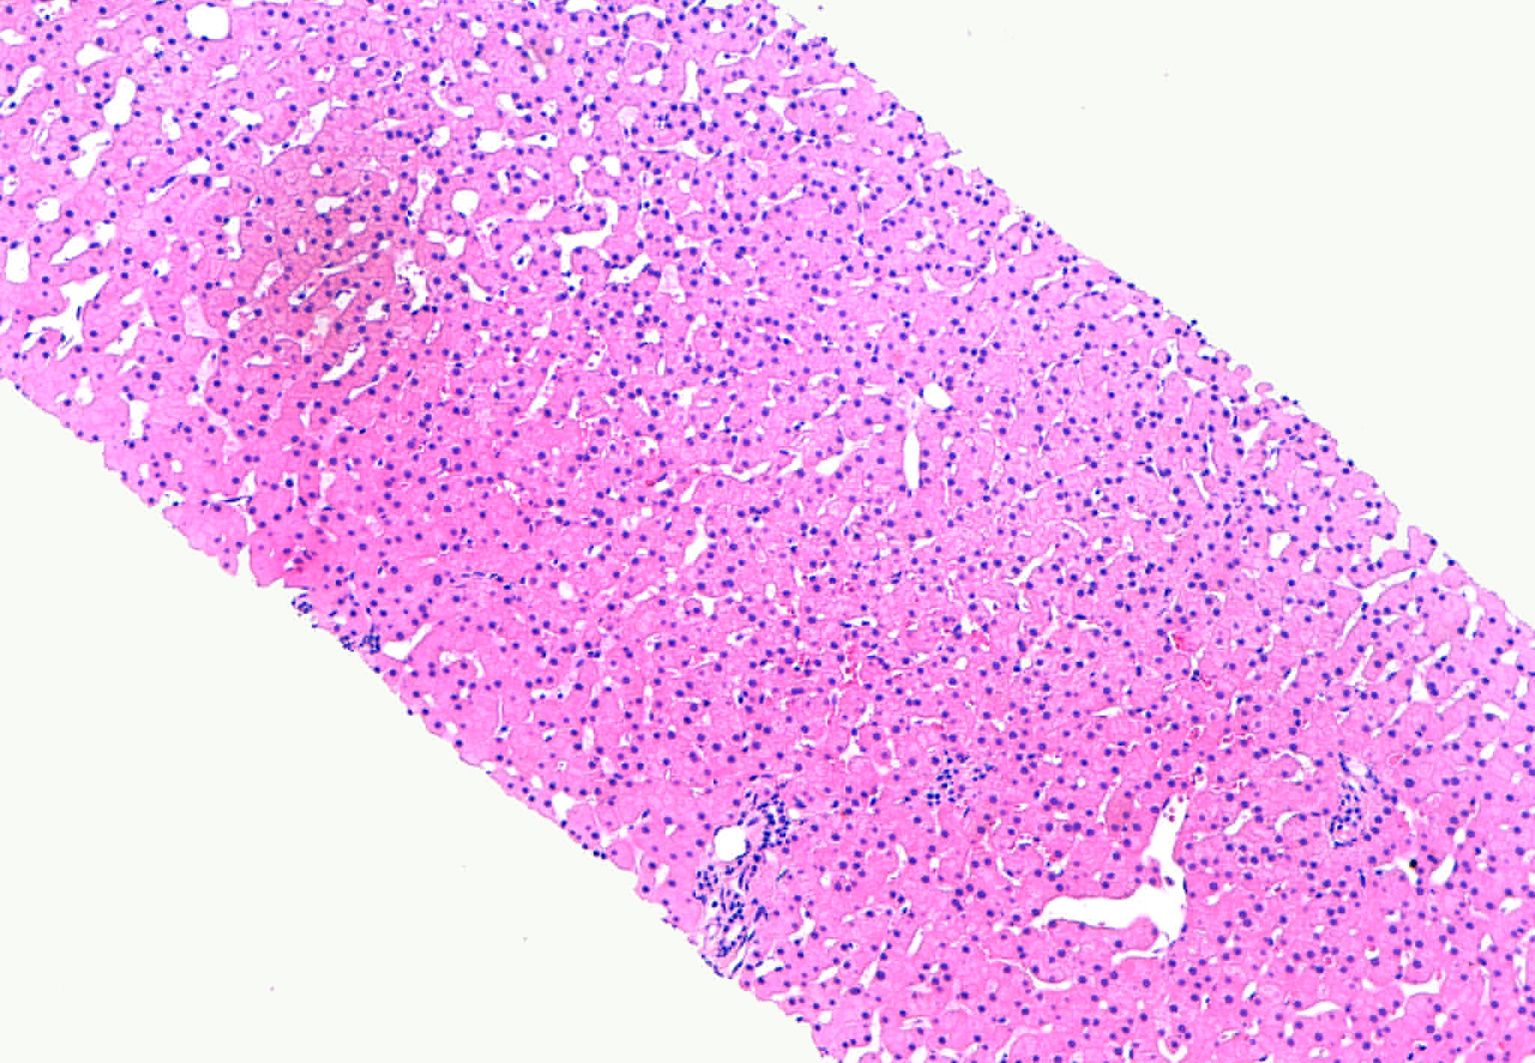

Los inmunosupresores se encuentran entre los grupos farmacológicos con mayor potencial teórico de inducir reacciones adversas, entre ellas las hepáticas. Presentamos el caso de un paciente de 35 años con enfermedad de Crohn en tratamiento con azatioprina por corticodependencia al que se le diagnosticó tras realización de una biopsia hepática de hiperplasia nodular regenerativa secundaria a este tratamiento.